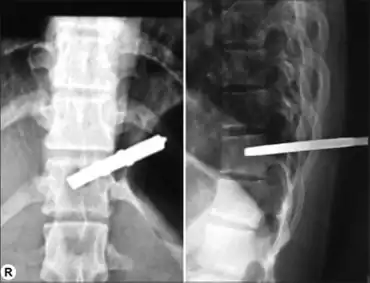

| a,b)Brown-séquard syndrome caused by a cervical synovial cyst. | |

Brown-Séquard syndrome may be caused by injury to the spinal cord resulting from a spinal cord tumor, trauma [such as a fall or injury from gunshot or puncture to the cervical or thoracic spine], ischemia (obstruction of a blood vessel), or infectious or inflammatory diseases such as tuberculosis, or multiple sclerosis. In its pure form, it is rarely seen. The most common cause is penetrating trauma such as a gunshot wound or stab wound to the spinal cord. Decompression sickness may also be a cause of Brown-Séquard syndrome.[3]